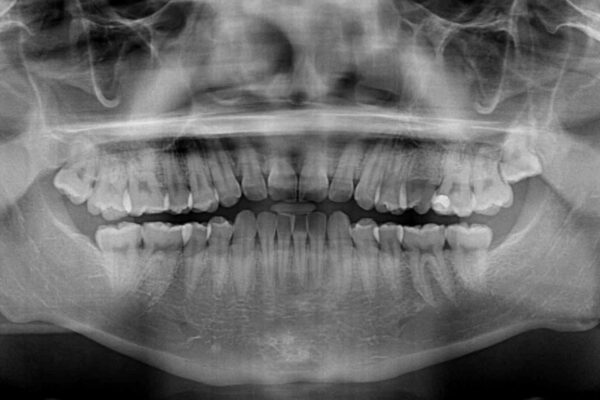

治療前

• 前歯のガタガタ・奥歯のかみ合わせ(シザーズバイト)を改善|1年半で完了したメタルブラケット矯正 治療前画像

・上顎左右の第二大臼歯が頬側へ転移し、シザーズバイト(scissors bite)の状態

・上顎左側第二小臼歯が90度捻転しており、噛み合わせに影響

主訴:前歯のデコボコと奥歯のかみ合わせを治したい 今回ご紹介するのは、「前歯のガタガタ(叢生)」と「奥歯のかみ合わせ(シザーズバイト)」にお悩みでご来院された患者様の症例です。 患者様は、 ・歯並びをできるだけ早く改善したい ・費用を抑えた矯正治療 というご要望をお持ちでした。